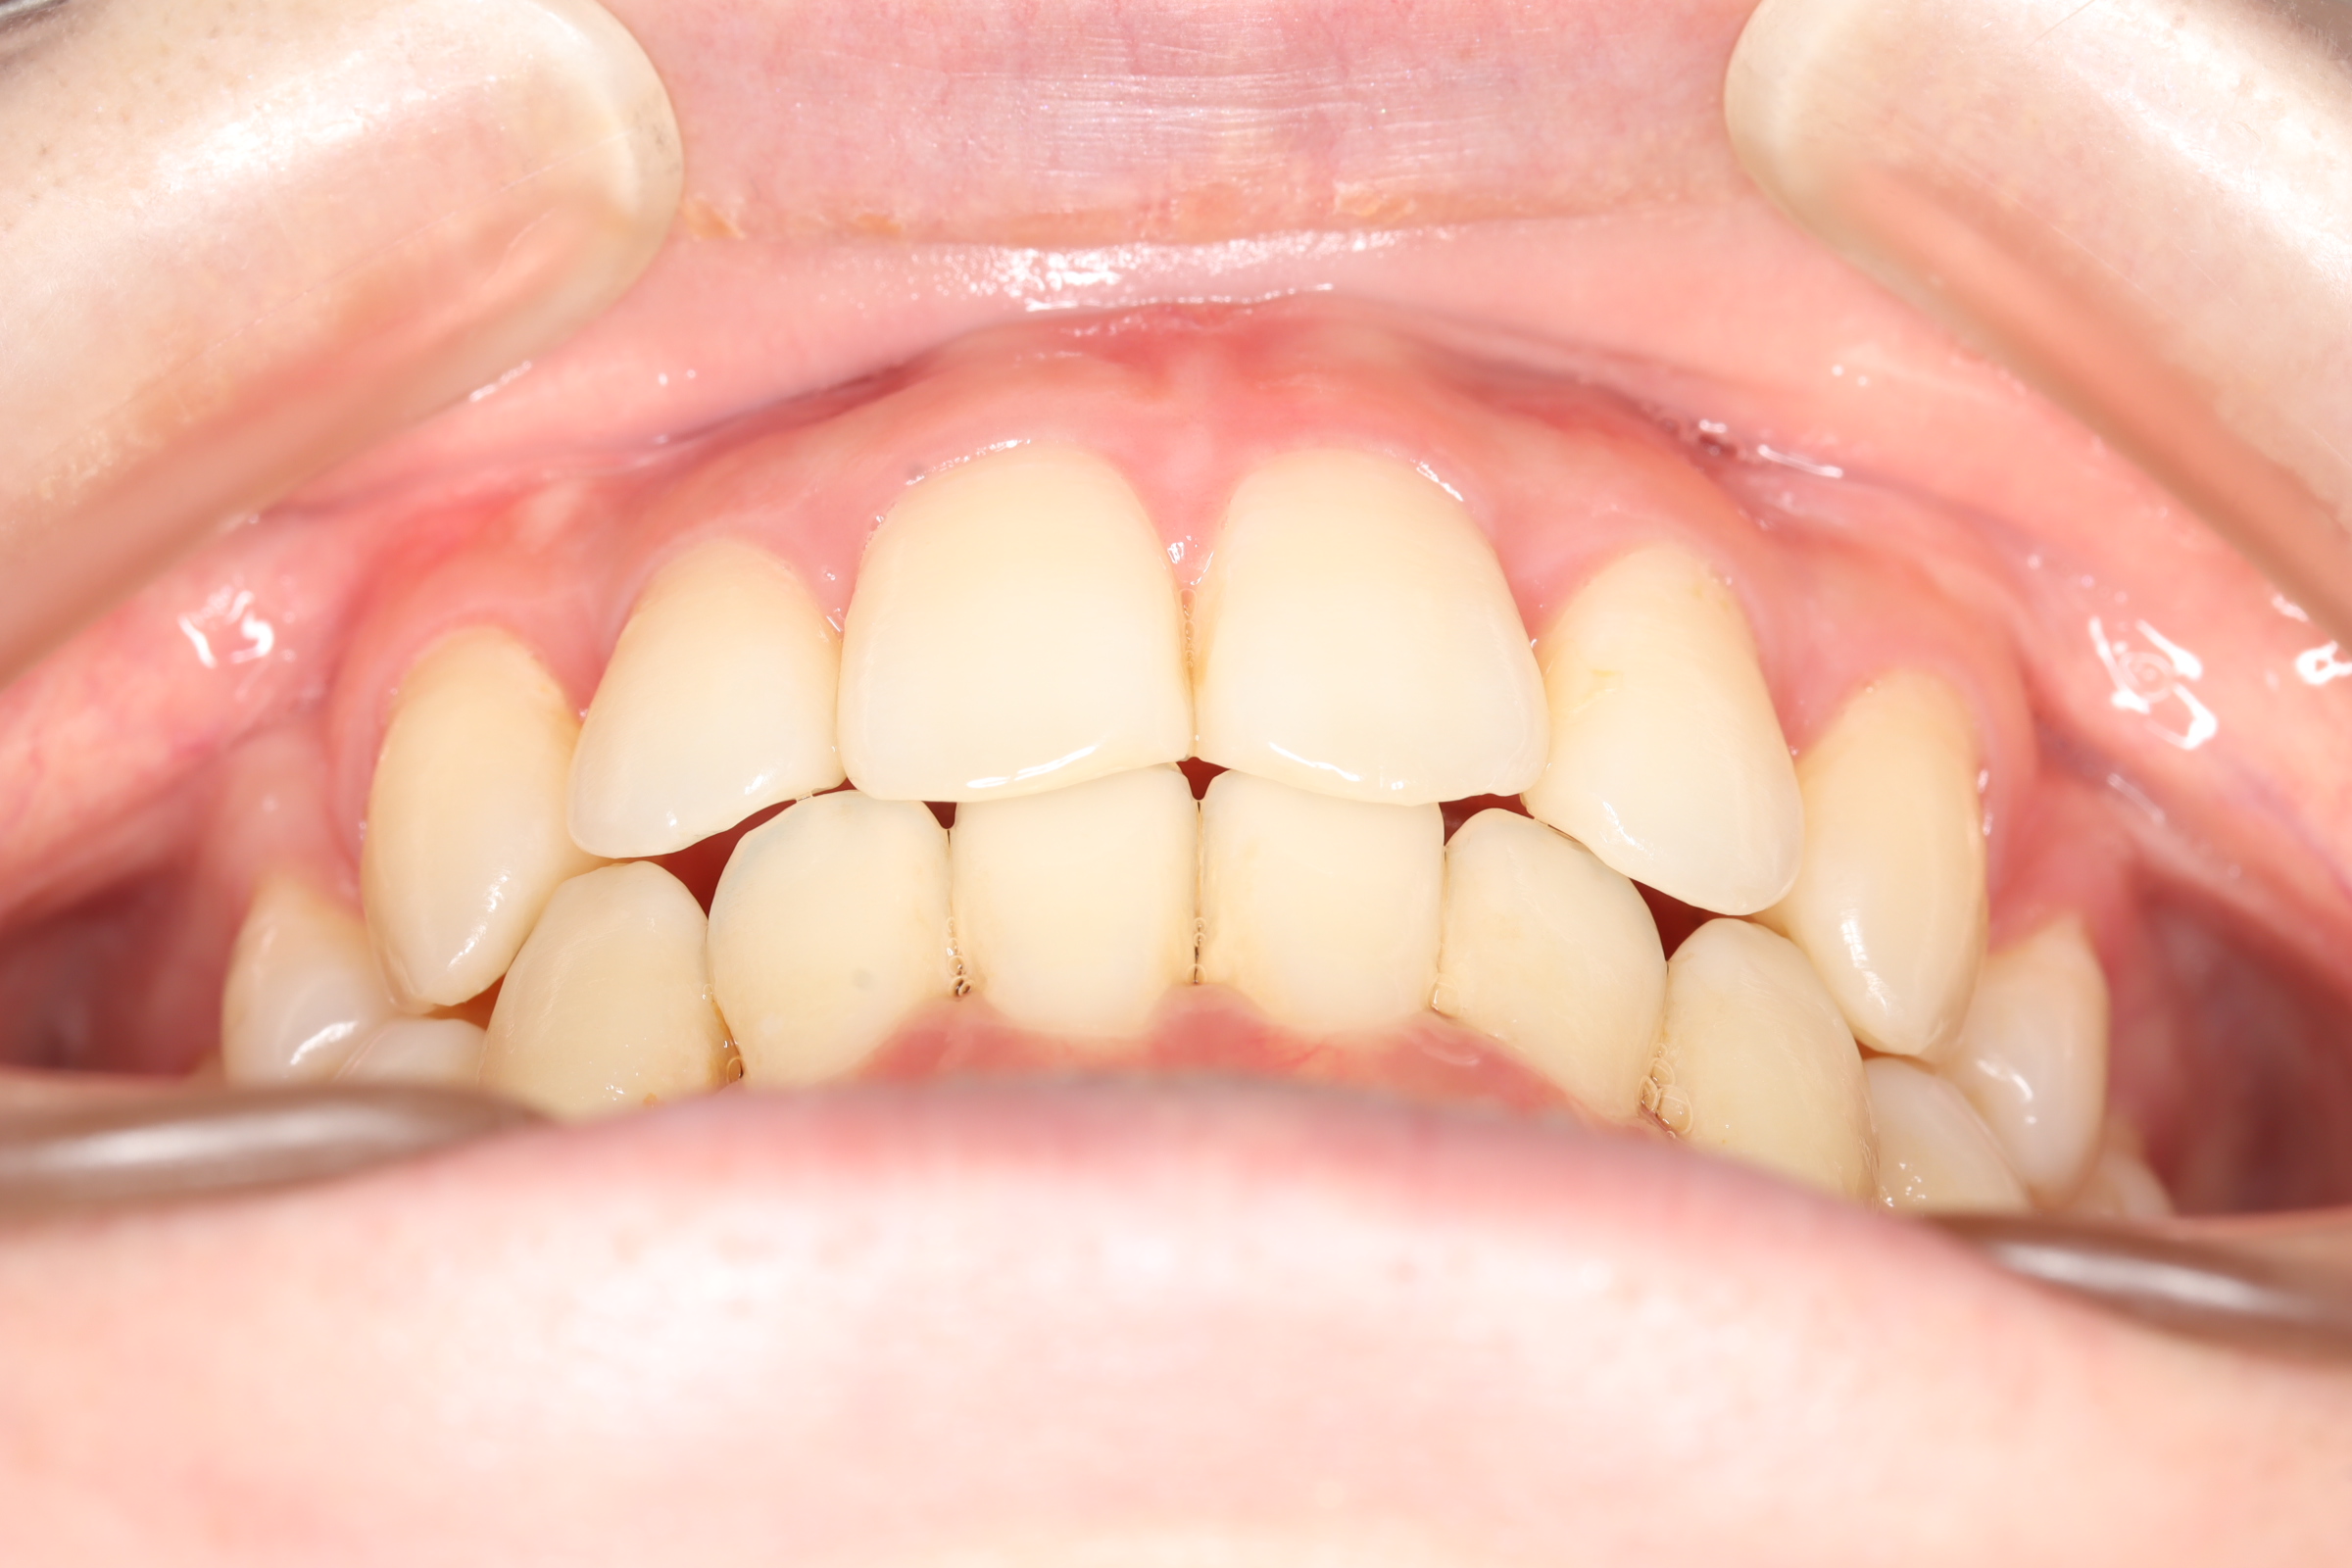

| 治療前 | SNSなどで「ガチャ歯」と呼ばれている、見た目のがたつきを治したかった患者さんです。 骨格的な問題はありませんでしたが、上下の前歯が唇側傾斜しており、上下顎前突症で口元の突出感がありました。 |

| 治療後 | 前歯から奥歯まで全体的に緊密な咬み合わせになっています。 歯のガタつきが無くなることにより、綺麗な見た目と歯磨きのしやすい口腔内環境になりました。 また突出感のあった口元もすっきりして綺麗なEラインとなり横顔も変化しました。 しっかりとしたかみ合わせを作ることにより、綺麗な歯並びになります。 |